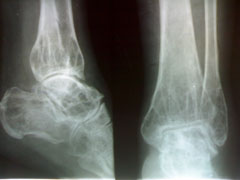

以下是引用杀毒软件在2009-7-17 11:54:00的发言:[br]骨软化症,内分泌性骨病,大骨节病均不能排除,请结合实验室检查。

以下是引用随光逐影在2009-7-17 15:12:00的发言:[br]甲状旁腺机能亢进引起多发性纤维囊性骨炎?

以下是引用zxl51642在2009-7-17 10:13:00的发言:[br]多关节骨质疏松并关节间隙狭窄,关节变形。考虑类风湿,结合病史及实验室检查(rf因子)。[br]

以下是引用dr.king在2009-7-18 20:57:00的发言:[br]甲状旁腺机能亢进引起多发性纤维囊性骨炎?进一步结合实验室检查。